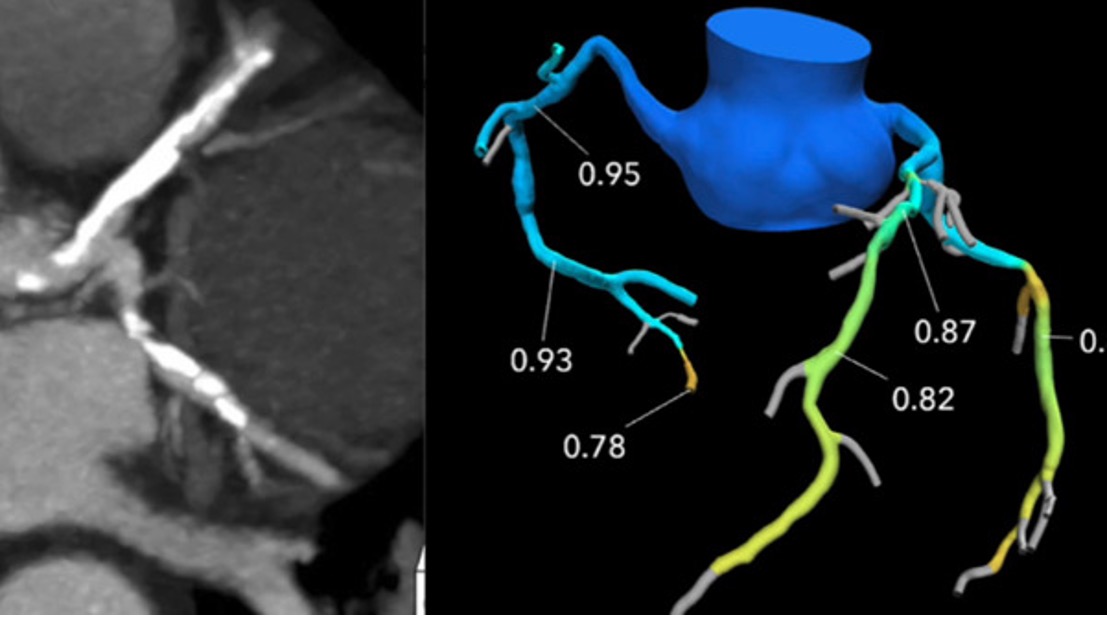

FFR-CT, or Fractional Flow Reserve derived from Coronary CT Angiography, is a non-invasive technique that uses CT scans to simulate the blood flow through coronary arteries, to assess the severity of blockages and guide treatment decisions. This provides your doctor with a 3D model of your coronary arteries (arteries that supply blood to your heart) as a way to identify any narrowing in the coronary arteries.

(FFRCT) is a physiologic simulation technique that uses routine CTA data to mathematically model coronary flow, pressure, and resistance

The most commonly used and approved technique, Heart Flow uses computational fluid dynamics (CFD) with off-site supercomputers. A patient-specific three-dimensional (3D) anatomic coronary artery model is obtained by using semiautomatic contouring and segmentation. A physiologic model is then derived based on patient-specific inflow and outflow hemodynamic conditions, with the resting myocardial blood flow proportional to the myocardial mass, and the microvascular resistance inversely proportional to the size of epicardial coronary arteries.

The addition of FFRCT to coronary CTA improves its specificity by evaluating lesion-specific ischemia, enhances its role as a gatekeeper for ICA by decreasing nonobstructive disease at ICA, and offers guidance for revascularization decisions and planning. The accuracy of FFRCT and superior specificity compared with that of coronary CTA has been well established on both off-site and on-site platforms in multiple studies.

An FFRCT value greater than 0.8 is normal, values between 0.76 and 0.8 are borderline, and a value less than or equal to 0.75 is abnormal.